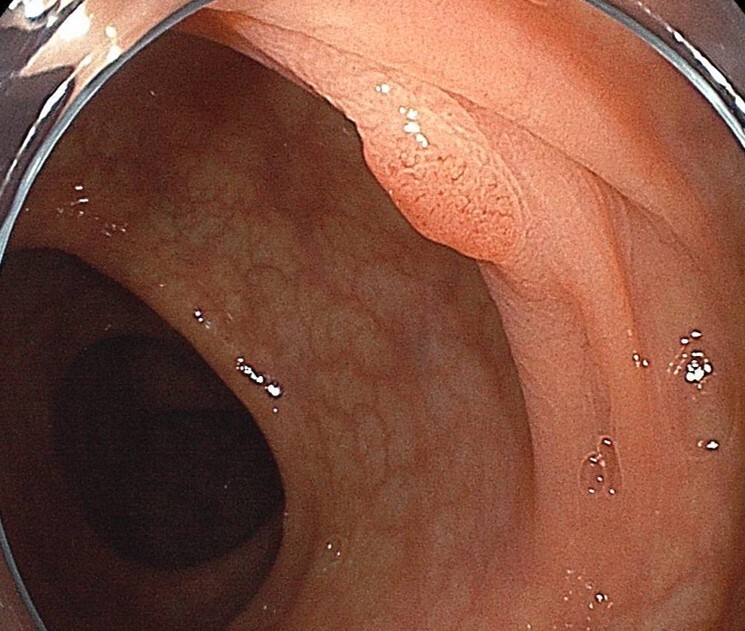

良性病変、当院で切除治療を行い根治

良性病変、他院で切除治療を行い根治

早期発見された大腸がん、内視鏡治療により根治

同じ病変、特殊光(BLI観察)による精密診断

血便あり受診、虚血性腸炎と診断。当院治療にて根治